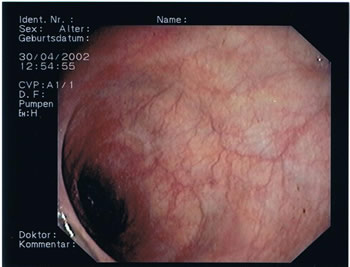

Endoskopische Bilder. Das Darmlumen innerhalb der einzelnen Darmabschnitte kann eher rundlich, leicht eingeengt oder dreieckförmig aussehen, entsprechend des anatomischen Aufbaus (s. Abb.1-4). Grundsätzlich gibt es verschiedene Arten von Polypen mit unterschiedlichen Konfigurationen und von verschiedener Größe. Kugelig(Abb.6) mit schmaler Verbindung zur Darmwand, hügelig mit breiter Basis, muschelförmig, die sich häufig an eine Querfalte anschmiegen, gestielte Polypen, die über einen Stiel mit der Darmwand verwachsen sind und sessile Polypen (Abb.5), die breitbasig auf der Darmwand aufsitzen. Der Übergang zum Dünndarm (Ileocaecal-Klappe) kann des Öfteren ein polypöses Aussehen vortäuschen (Abb.4).